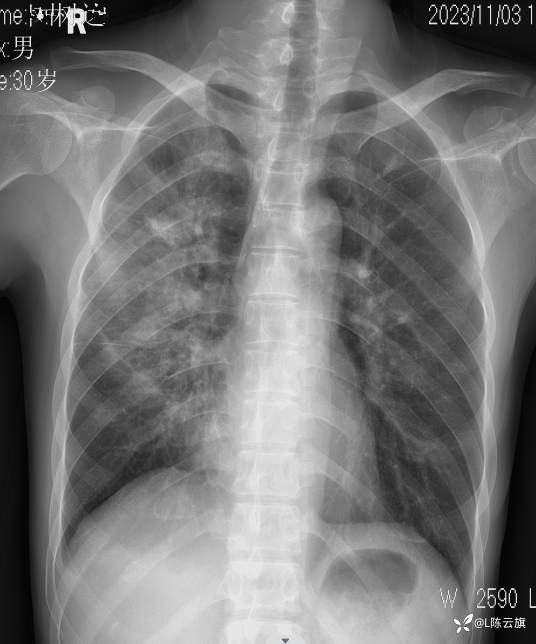

病例[每周胸片] 207 正侧位胸片 该如何诊断?(结果已公布)

患者男,30岁,精神病长期住院患者。咳嗽、咳痰二天伴发热、胸痛,体温38.5度。听诊两肺干湿啰音。